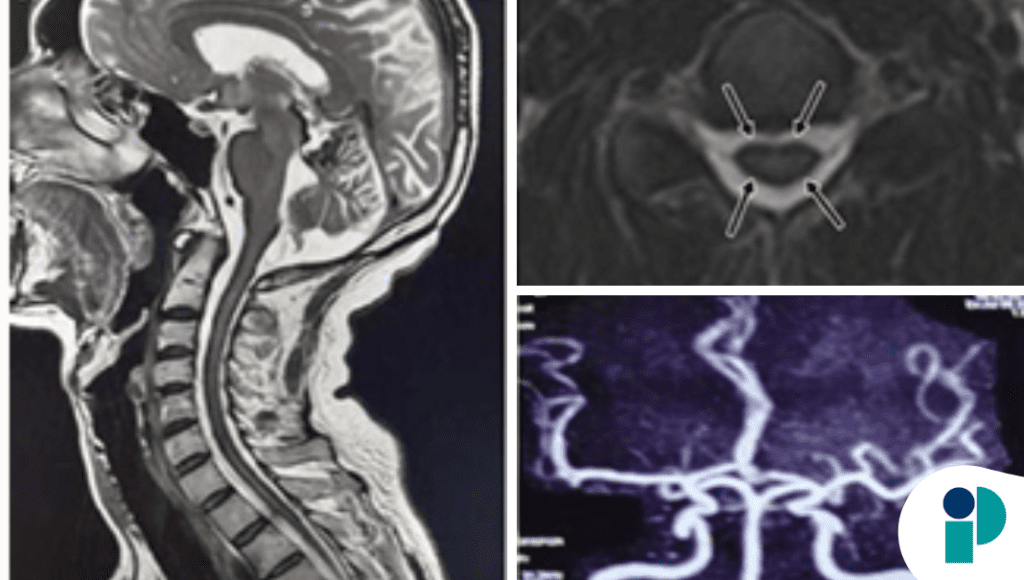

El cuadro clínico se caracterizó por trastorno del equilibrio, deterioro motor gradual y progresión lenta de síntomas neurológicos, manifestaciones típicas de daño neurodegenerativo secundario a exposición crónica al hierro libre en el líquido cefalorraquídeo. La resonancia magnética fue determinante al mostrar un patrón lineal hipointenso en superficies cerebelosas y estructuras del sistema nervioso central, hallazgo distintivo de siderosis superficial.

Los autores señalan que la condición suele originarse por sangrado subaracnoideo crónico de bajo grado, frecuentemente relacionado con defectos durales, malformaciones vasculares o lesiones previas del sistema nervioso. La identificación de la fuente de sangrado es fundamental porque permite intervención dirigida para frenar la progresión neurológica, aunque el daño establecido puede ser irreversible.